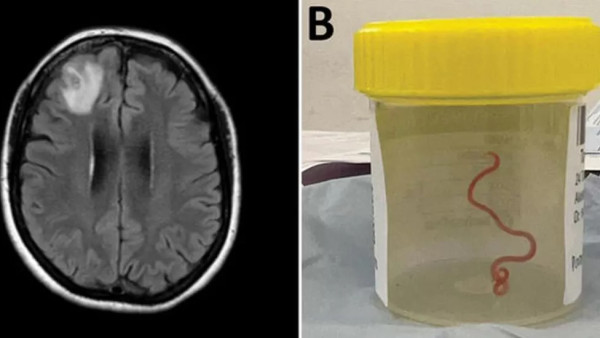

果然不出所料,從腦部掃描結果可以見到,患者的額葉發出奇怪的光,醫生便決定立即對其大腦進行活組織檢查。手術期間,醫生發現一條類似長繩的物體,拔出後發現竟是一條8厘米長,而且仍活著的寄生蟲。

塞納納亞與同事之後在9月份發表報告時表示,這條寄生蟲名為Ophidascaris robertsi,主要宿主是蟒蛇,這名澳洲女子是有紀錄以來的人類感染首例。